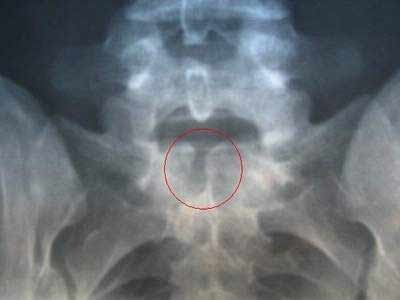

Gai cột sống là sự phát triển thêm ra của xương trên thân đốt sống, đĩa sụn, dây chằng quanh khớp do viêm khớp cột sống mạn tính, chấn thương hay sự lắng đọng can-xi ở các dây chằng, gân tiếp xúc với đốt sống.

Vị trí thường mọc gai là mặt trước và bên của cột sống, hiếm khi mọc ở phía sau nên ít chèn ép vào tủy và rễ thần kinh. Gai cột sống khiến người bệnh rất khó chịu, nhất là cảm giác đau ở vùng thắt lưng, đau vai hoặc cổ do gai tiếp xúc với dây thần kinh, các xương đốt sống khi cử động, đau lan xuống cánh tay, tê chân tay, đôi khi làm giới hạn vận động.